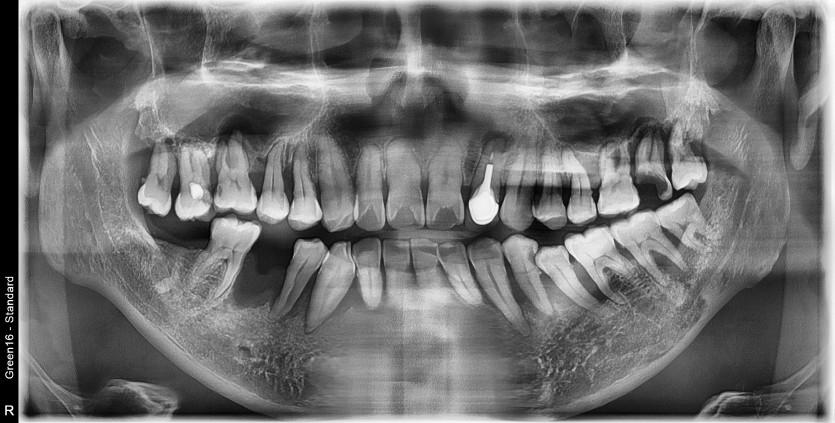

하악 전체 임플란트 증례입니다.(상악 일부)

14개의 임플란트로 완성하였습니다.